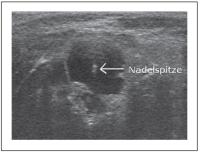

Zyste - Ultraschallgezielte Feinnadelpunktion

Abbildung 9: Ultraschallgezielte Feinnadelpunktion einer Zyste: Die Lage der Nadelspitze wird sonographisch dokumentiert.

Keywords: FeinnadelpunktionZyste